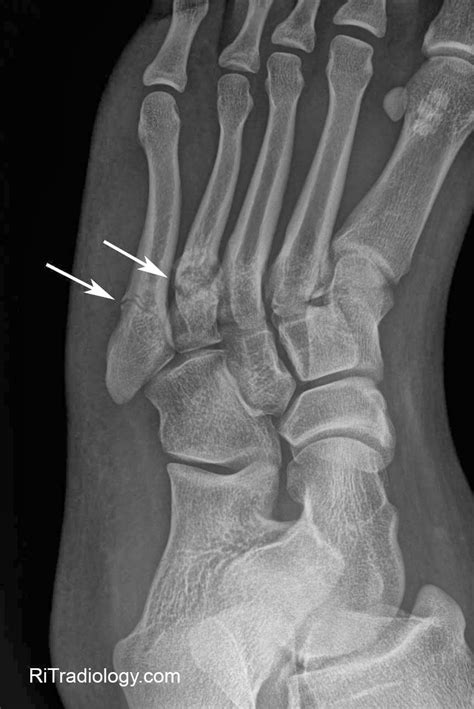

RiT radiology: Metatarsal Stress Fracture

fracture metatarsal stress foot oblique radiology fifth metatarsals proximal